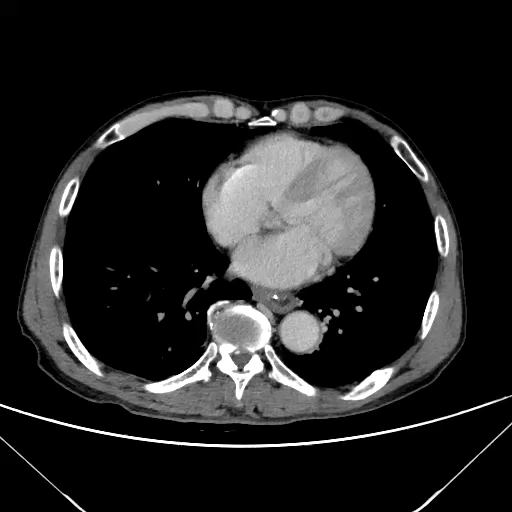

进食苹果,腹痛难忍!大家来找找怎么回事?

主诉:腹痛3h

简要病史:患者于3小时前进食苹果后不久出现腹痛,为上腹及左上腹持续性疼痛无缓解,疼痛难忍,无他处放射,伴腹胀,无恶心、呕吐,无发热,无头晕等其他不适。

辅助检查:CT平扫及增强检查

相隔两小时后行CT增强

动脉期

静脉期

延迟期

请诊断?